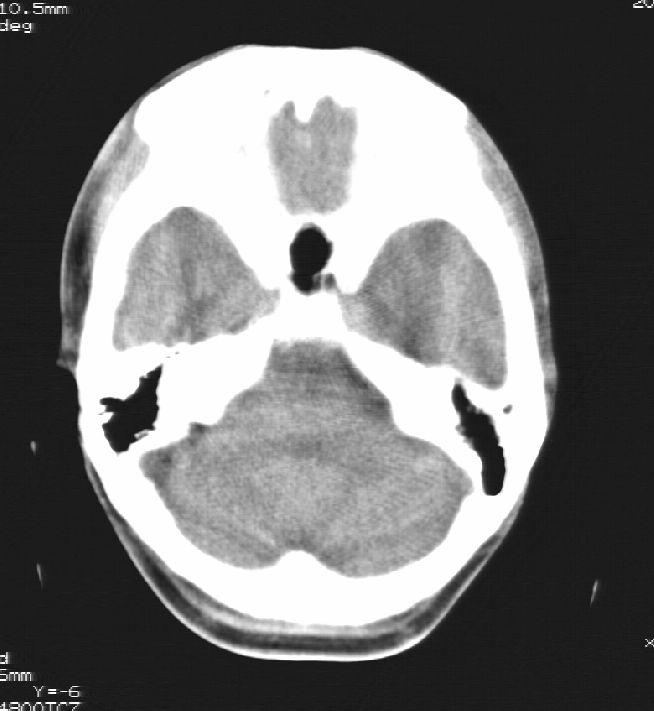

胼胝体发育不全合并 透明隔缺如 、脂肪瘤。

胼胝体发育不全合并脂肪瘤;建议必要时行mri检查。

脑水肿,头皮下血肿,胼胝体发育不全、合并脂肪瘤及钙化;建议必要时行mri检查。

胼胝体发育不全、合并脂肪瘤及钙化。